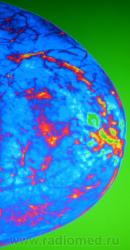

Возможности "цветовой" обработки цифрового изображения молочной железы.

Еще одна серия.